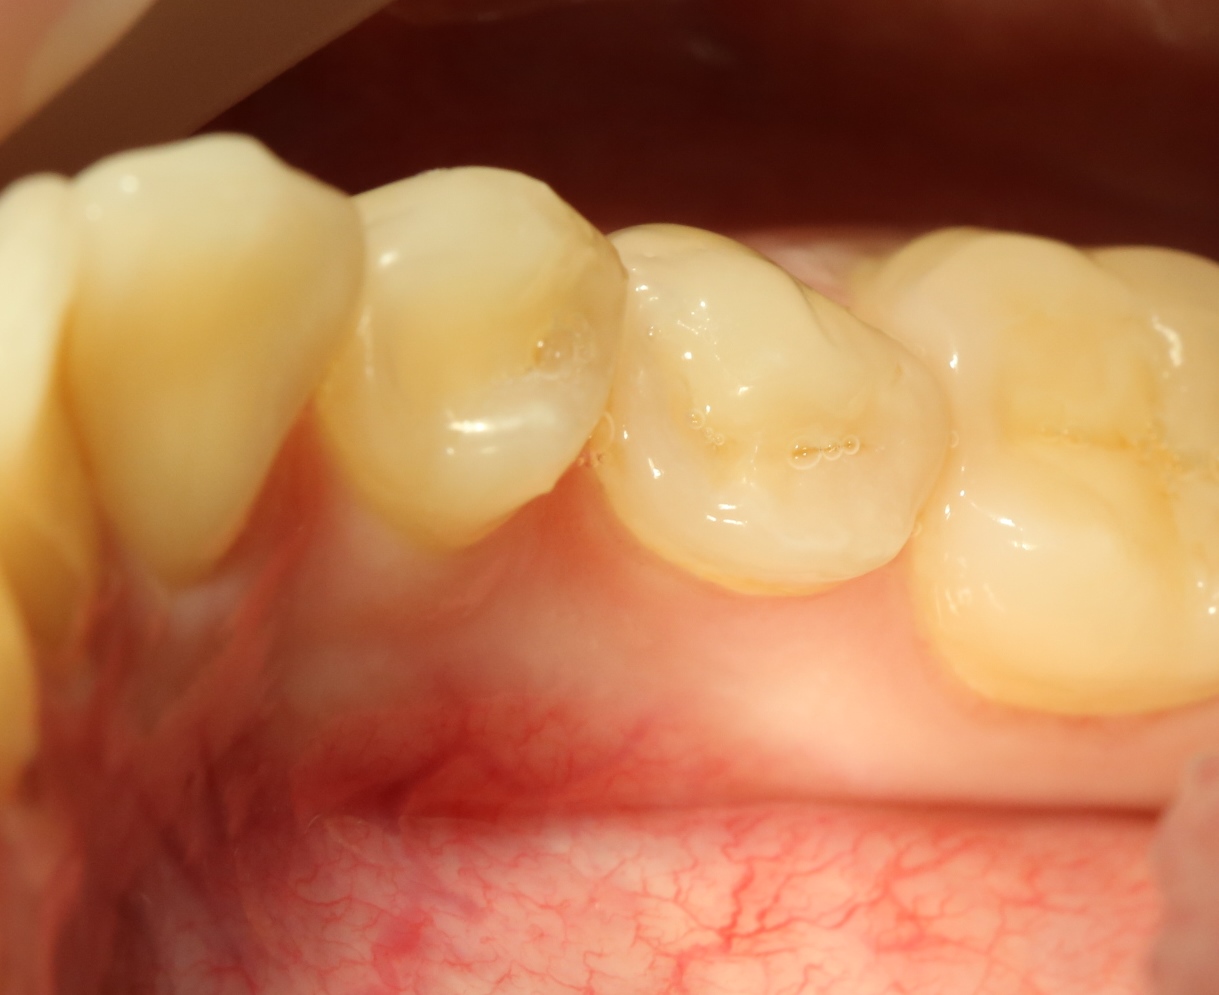

А вот фотография через месяц после операции:

Задайтесь вопросом — оно того стоило? 30 минут в операционной, 4 дня на реабилитацию и 2 недели со швами? Стоило ли это того, чтобы в будущем избежать серьезных проблем со здоровьем?

На мой взгляд — да.